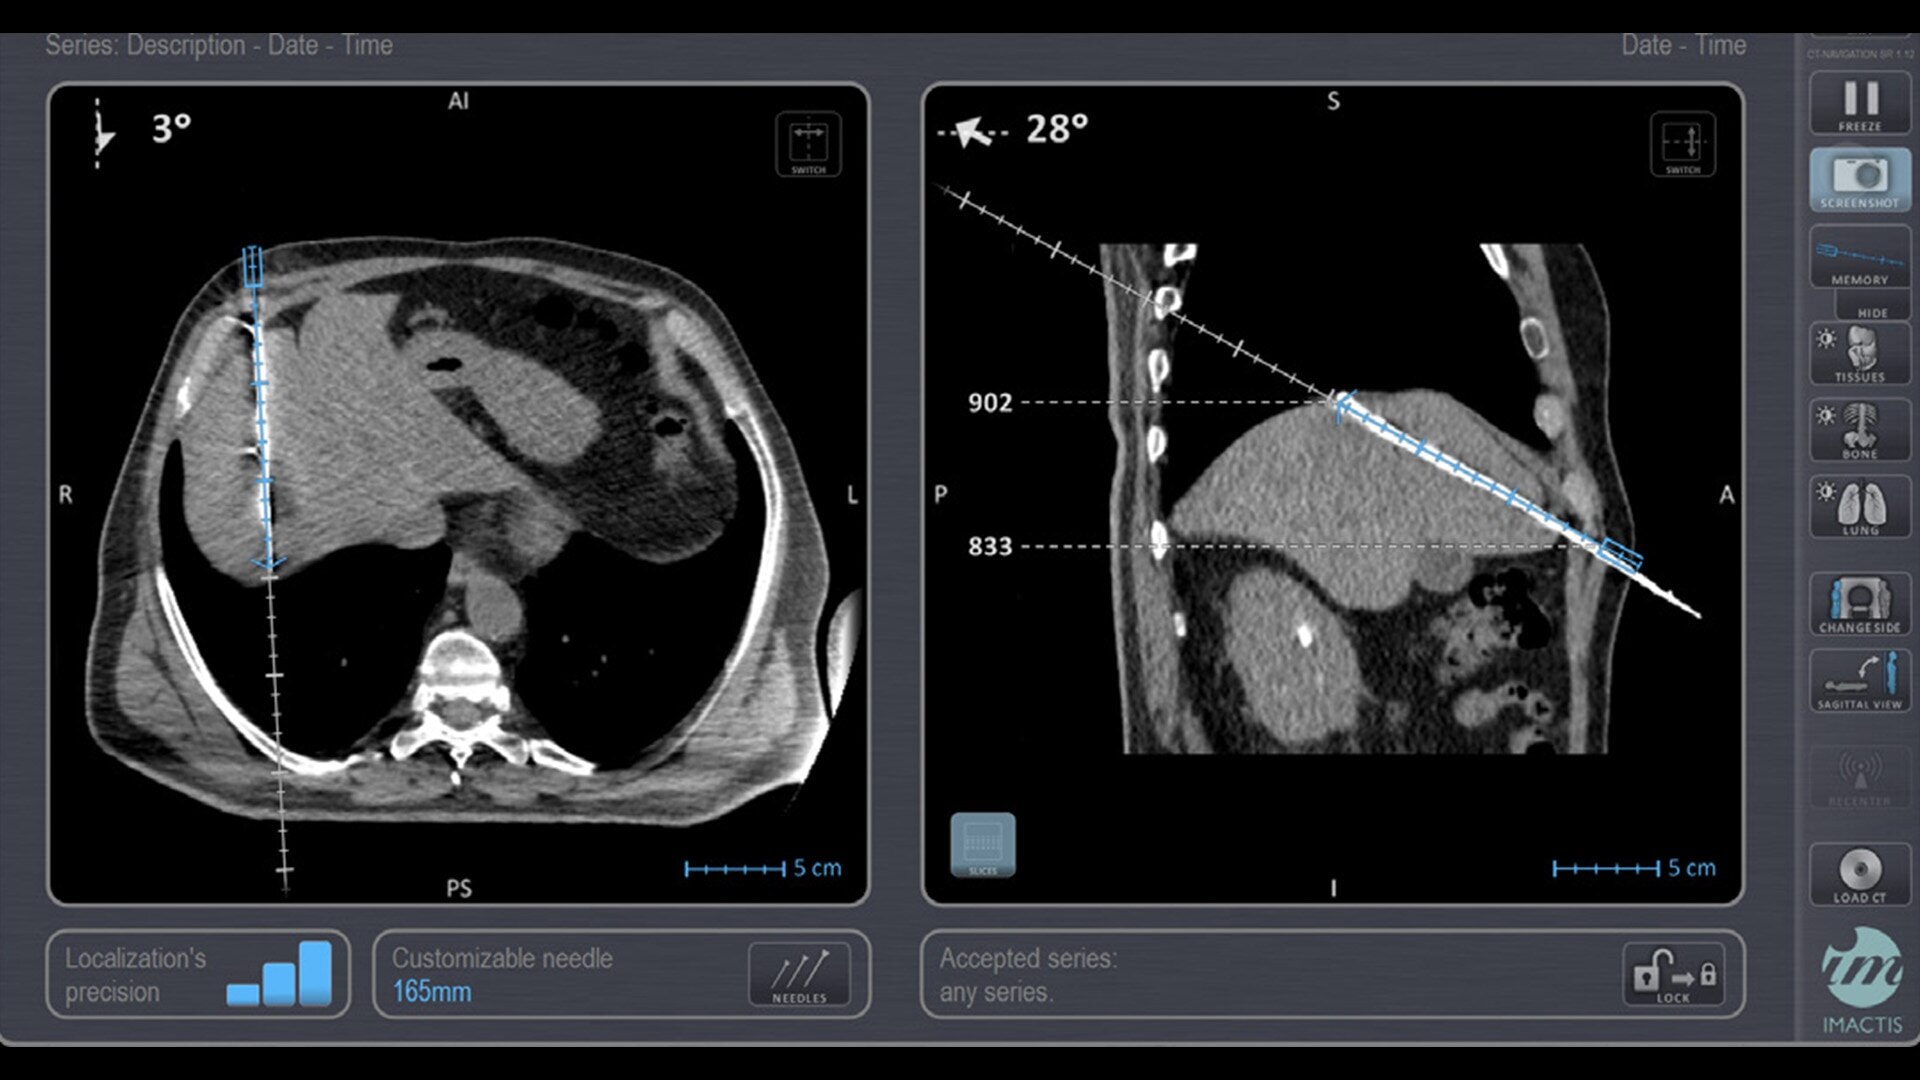

In interventional radiology, the success of the percutaneous procedure depends on correct needle positioning. The Imactis system helps the radiologist place one or more needles with great accuracy, in less time and with fewer control scans.

Imactis enables you to find the ideal path to the target.

With real-time image reconstruction, live interactive navigation and no limit in angulation, the optimal clinical choices are clear.

Live 3D needle tracking, precise reproduction of your planned trajectory and continuous needle depth measurement help ensure optimal needle placement.